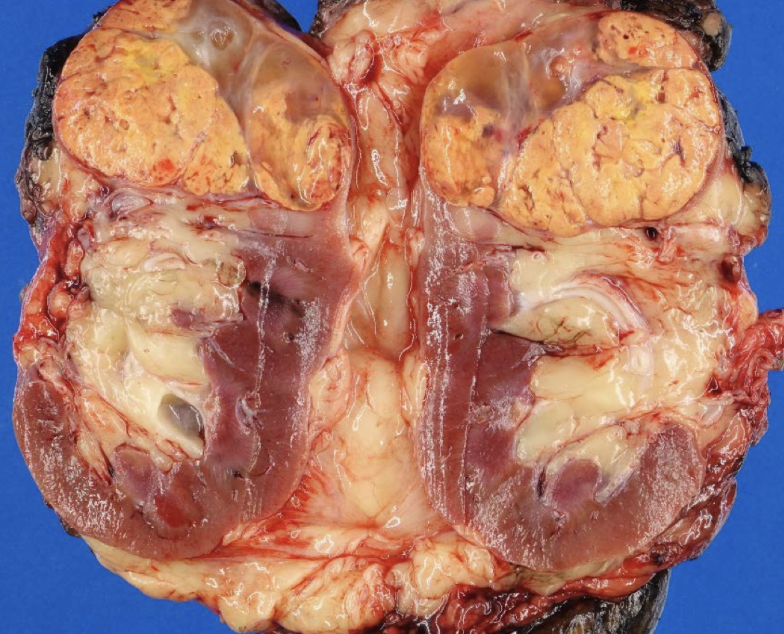

papillary RCC

arise from distal convoluted tubules

multifocal and bilateral

MET

proto-oncogene that encodes the tyrosine kinase receptor for hepatocyte growth factor

papillary RCC

papillary vs. clear cell: multifocal

papillary RCC

papillary vs. clear cell: arise in distal tubular epithelium

papillary RCC

papillary RCC

papillary RCC

RCC type: +7 (met), +17, -Y